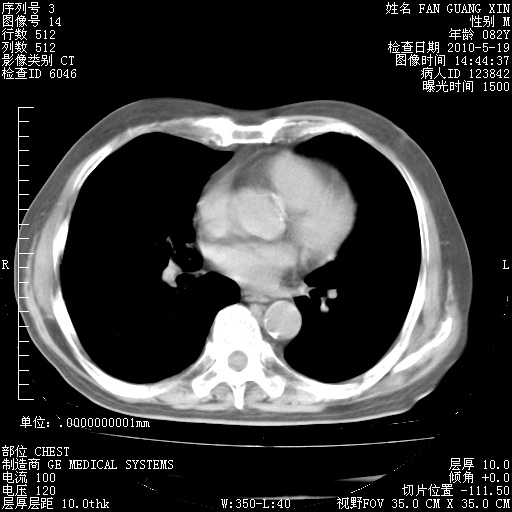

复查肺部CT,明显好转。为什么发热呢?

治疗3周后的肺部CT

治疗3周后的肺部CT纵隔窗